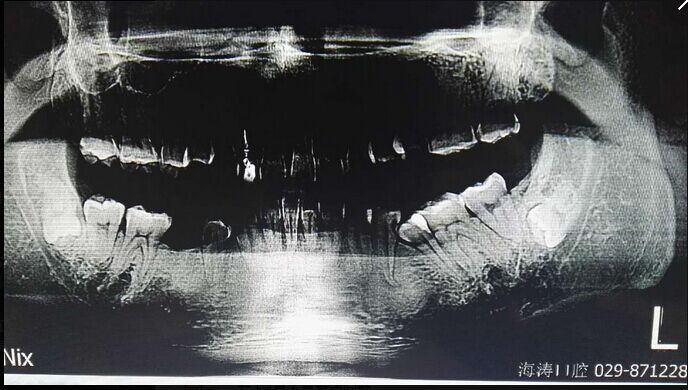

倒置阻生牙拔牙的病案討論

討論四:片子顯示的倒置阻生牙撥牙關(guān)健注意幾點(diǎn),1.翻瓣后去骨部位盡量離7遠(yuǎn)中,別破壞7遠(yuǎn)中骨壁,避免損傷7,以去除8根部的阻力為主。2.暴露阻生牙后,用鉆磨斷部分冠根后,用小骨鑿劈裂冠與根,可避免牙鉆因視野而誤傷神經(jīng)。3.冠根裂開(kāi)后,先用牙挺挺出根部,然后挺出冠部。

提問(wèn):對(duì)7號(hào)牙沒(méi)有影響的埋伏智齒,是不是可以不拔?

答:一般情況下,完全骨埋伏阻生牙患者如無(wú)不適癥狀不會(huì)要求撥牙的,很多時(shí)候是口腔內(nèi)其它問(wèn)題拍片時(shí)發(fā)現(xiàn),但醫(yī)生發(fā)現(xiàn)這種情況要告知患者將來(lái)可能會(huì)發(fā)生什么問(wèn)題,例如頜骨囊腫,7號(hào)牙松動(dòng)等等,畢竟這個(gè)8號(hào)牙是潛在的病灶牙,究竟撥與不撥得讓患者作主,我們得盡到告知義務(wù)。往往最后決定撥這類(lèi)牙的患者都是有各種不適癥狀的。

至于對(duì)7號(hào)牙暫時(shí)沒(méi)有影響的埋伏牙,不等于以后永遠(yuǎn)不影響。